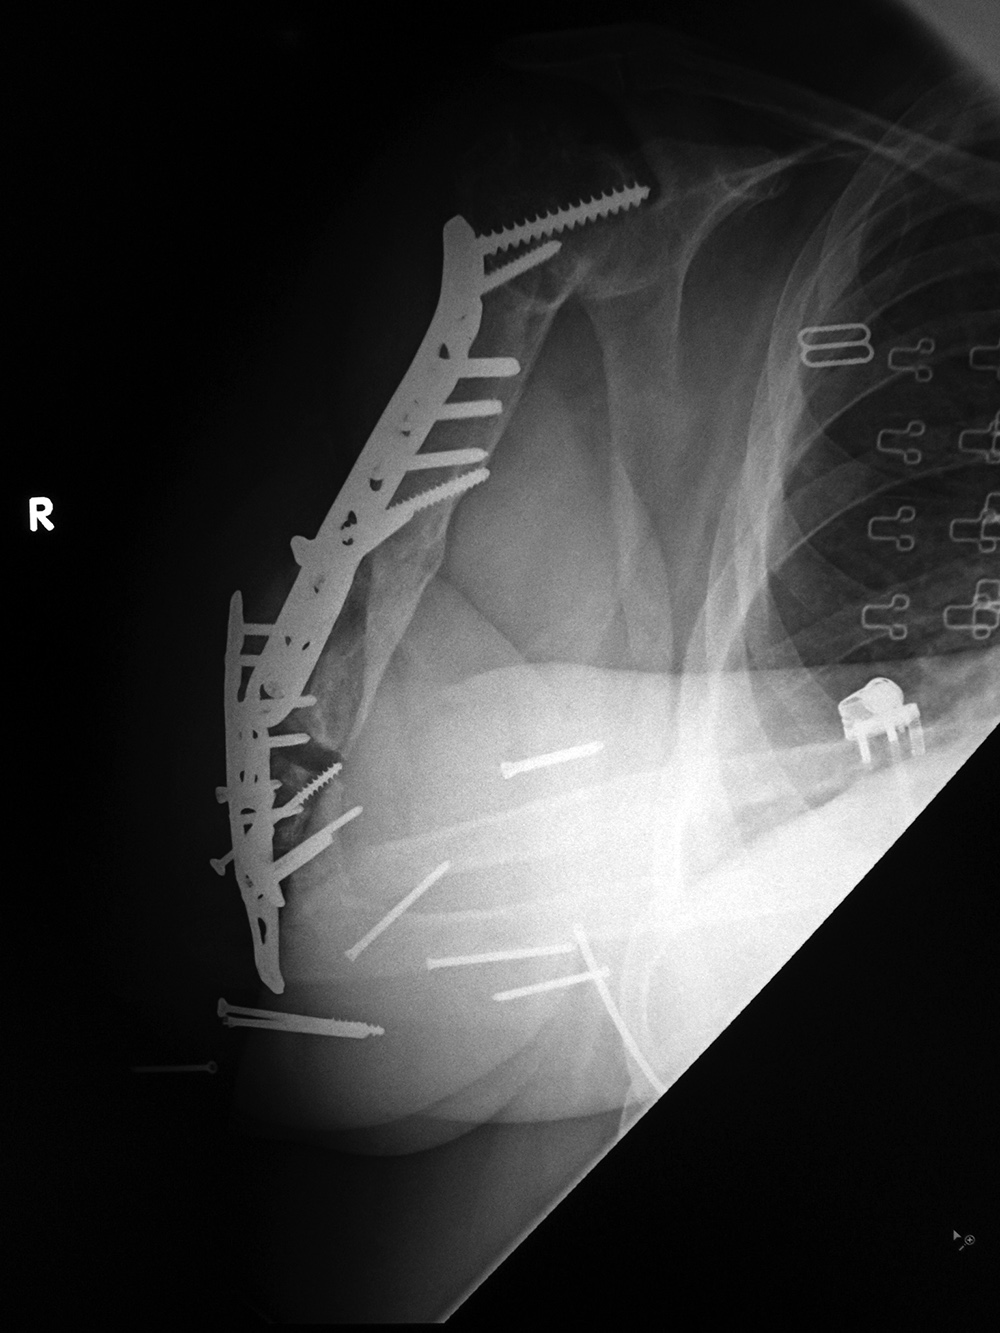

| Right femur periarticular plate breakage and chronic fracture nonunion |

| 36 year-old man with bullet wound in 2003 complicated by femur fracture infected non-union treated by multiple attempts with external fixation and open reduction and internal fixation (ORIF). Radiography 12 years later shows chronic fracture hypertrophic nonunion, multiple shrapnel fragments, and breakage of a periarticular fixation plate. |